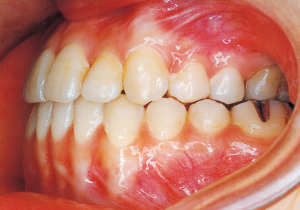

Age at Initial Visit: 8 years 1 month, Female / Protruding lower bite. Protruding lower jaw

Although there were many missing deciduous teeth, the number of permanent teeth was not problematic (4). The amount of negative overjet was significant (1). On cephalometric radiographs, the mandibular ramus was not relatively long, but the large gonial angle and the long mandibular body were noticeable, indicating an overall tendency of the mandible to project inferiorly and anteriorly. High lower facial height was also characteristic.

A potential predisposition to mandibular protrusion was clearly evident.